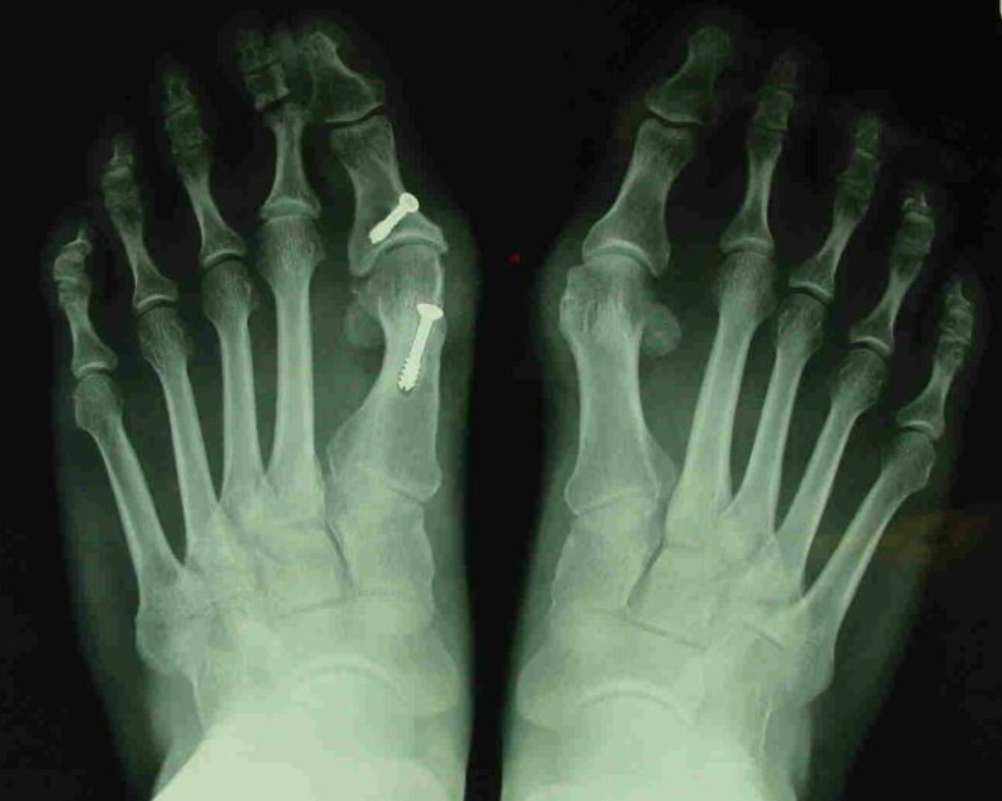

무지외반증을 치료하는 수술 방법은 무려 100가지가 넘는다고 합니다. 이는 환자마다 무지외반증의 원인, 변형된 모양과 각도가 다 다르기 때문에 한 가지 방법으로 모든 환자를 치료할 수 없다는 것입니다. 수술은 휘어져 있는 엄지발가락을 올바른 방향으로 맞춘 후 핀이나 나사 등으로 고정하는 방법이 사용됩니다. 뼈를 치는 수술이다 보니 수술 후 통증이 있을 수 있으며, 수술 후 얼마 기간 동안은 깁스를 하고 생활해야 하며, 병원을 퇴원한 후에도 수술부위에 충격이 가거나 움직이지 않도록 주의해야 합니다.